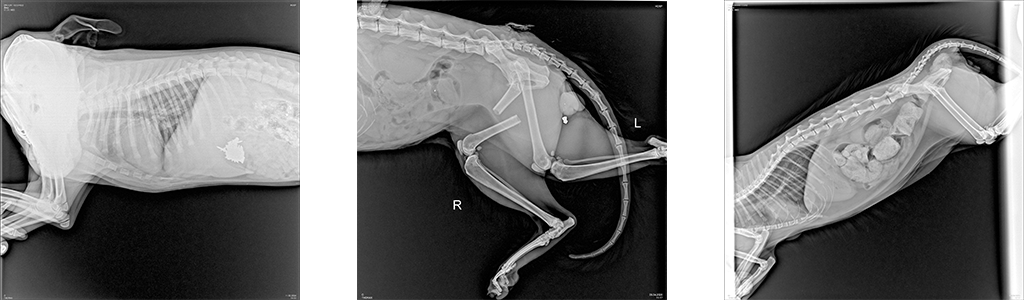

- Для исключения патологий опорно—двигательного аппарата: переломов, дегенеративных изменений костной и хрящевой ткани, дисплазии тазобедренного и локтевого суставов, новообразований костей и ряда других патологий.

Возрастные животные особенно часто подвергаются риску развития патологии, при которой происходит разрушение суставного хряща, рентгенография помогает определить явные изменения в суставах, такие как: износ хряща, образование костных наростов -остеофитов.

- Для определения патологий органов грудной клетки: легких, сердца, наличия инородных тел в пищеводе. Рентген-диагностика применяется при таких симптомах у животного, как: проблемы с дыханием, обусловленные наличием воспалительных процессов, новообразований, скоплением жидкости в легких (плевральный выпот); сердечная недостаточность, изменение размеров сердца, например его увеличение или кардиомегалия, пневмоторакс (скопление воздуха в грудной клетке), гидроторакс (скопление жидкости в грудной клетке).

- При патологиях органов брюшной полости: кишечной непроходимости, вызываемой обструкцией кишечника проглоченными животным инородными телами или при развитии новообразований/опухолей кишечника. Если животное проглотило несъедобный предмет (игрушку, кость и др), который не вышел естественным путем и вызвал обструкцию, застрял в пищеварительном тракте, рентген-диагностика будет показана в качестве методов исследования первого выбора в комплексе с УЗ-диагностикой, и даст ветеринарному врачу информацию о местоположении инородного тела, его размере и структуре, а также поможет определиться с тактикой лечения. В целях исключения инородного предмета/тел в желудочно-кишечном тракте животного применяется рентгенография с контрастным веществом, которая требует больших временных затрат и подготовки в виде применения у животного контрастного вещества, но чрезвычайно эффективна и распространена в ветеринарной практике.

- При исследовании позвоночника — с помощью рентгенографии особенно в случае появления у животного неврологических симптомов, хромоты, болей в области спины и двигательных расстройств определяют патологические изменения костной системы и их источники: дегенеративные заболевания позвоночника, такие какие спондилез или артроз; деформации позвоночника.

- Рентген-диагностика у животных на определение беременности и количества плодов. В отличие от людей, у животных рентген-диагностика активно применяется в случаях, когда необходимо не только подтвердить или исключить факт наступления беременности у животного, но и с большей точностью, чем при УЗ-диагностики, определить количество плодов при беременности. Именно цифровая рентгенография полностью безопасна для самой будущей матери и ее потомства в этом случае.